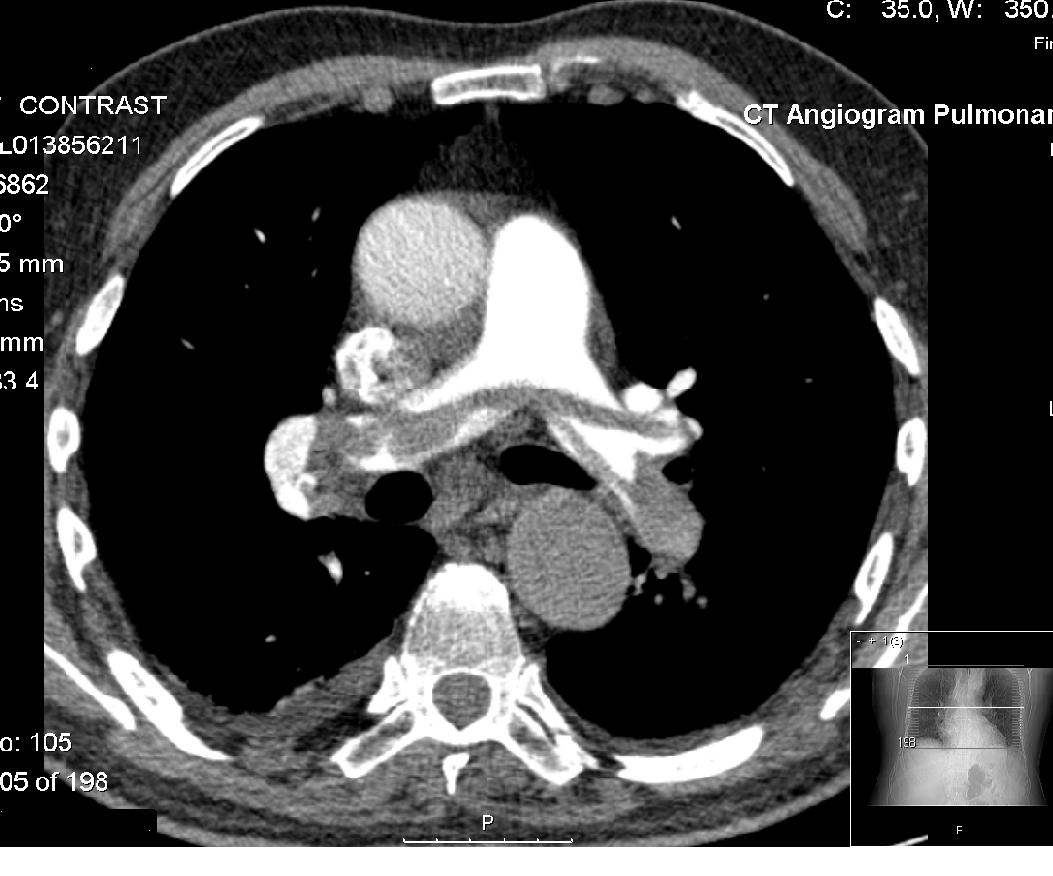

From en.wikipedia.org

CT pulmonary angiogram Wikipedia What Does A Chest Ct Angiogram Show Learn about the preparation, procedure, benefits, risks, and limitations of cta. A computerized tomography (ct) coronary angiogram is an imaging test that looks at the arteries that supply blood to the heart. Learn how to prepare, what to expect and what the results. Cta uses ct scanning and contrast material to examine blood vessels in various parts of the body,. What Does A Chest Ct Angiogram Show.